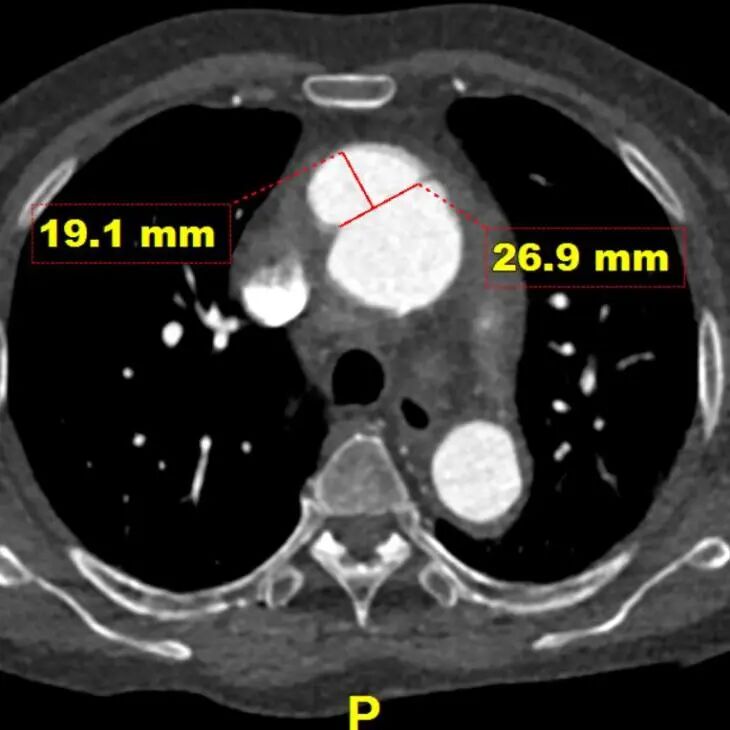

术前CTA

患者入院后行CTA检查,可见患者升主动脉巨大溃疡伴血肿,弓降部多发溃疡。无名动脉前缘至窦管交界大弯侧95.3mm,小弯侧54.7mm。

溃疡深度及宽度

gore医疗怎么样「胸有乾坤」异“区”同“功” 精准定位——GORE® TAG® 可主动调控胸主动脉覆膜支架治疗升主动脉穿透性溃疡病例报道_https://www.jmylbn.com_新闻资讯_第10张